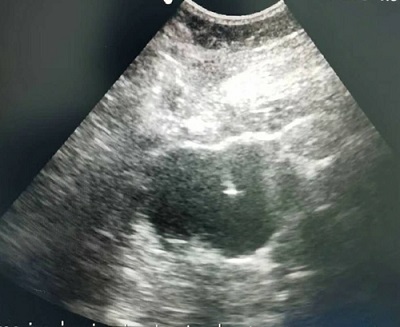

正在做超聲介入技術(shù)治療

泌尿普通外科副主任付東方、醫(yī)師劉洋、超聲醫(yī)學科主任班瑩瑩三位醫(yī)師密切配合,在彩超下準確無誤的定位,精確引導,在局麻下行彩超引導左腎囊腫經(jīng)皮穿刺引流術(shù),穿刺針插入囊腔抽吸囊液80ml,行蛋白凝固實驗陽性,隨即在囊腔內(nèi)注入無水酒精硬化,將囊腫內(nèi)壁細胞的功能破壞,達到永久治愈的目的。術(shù)后復查超聲囊腫未探及,輕松解決了馮奶奶的痛苦。

超聲介入技術(shù)治療腎囊腫